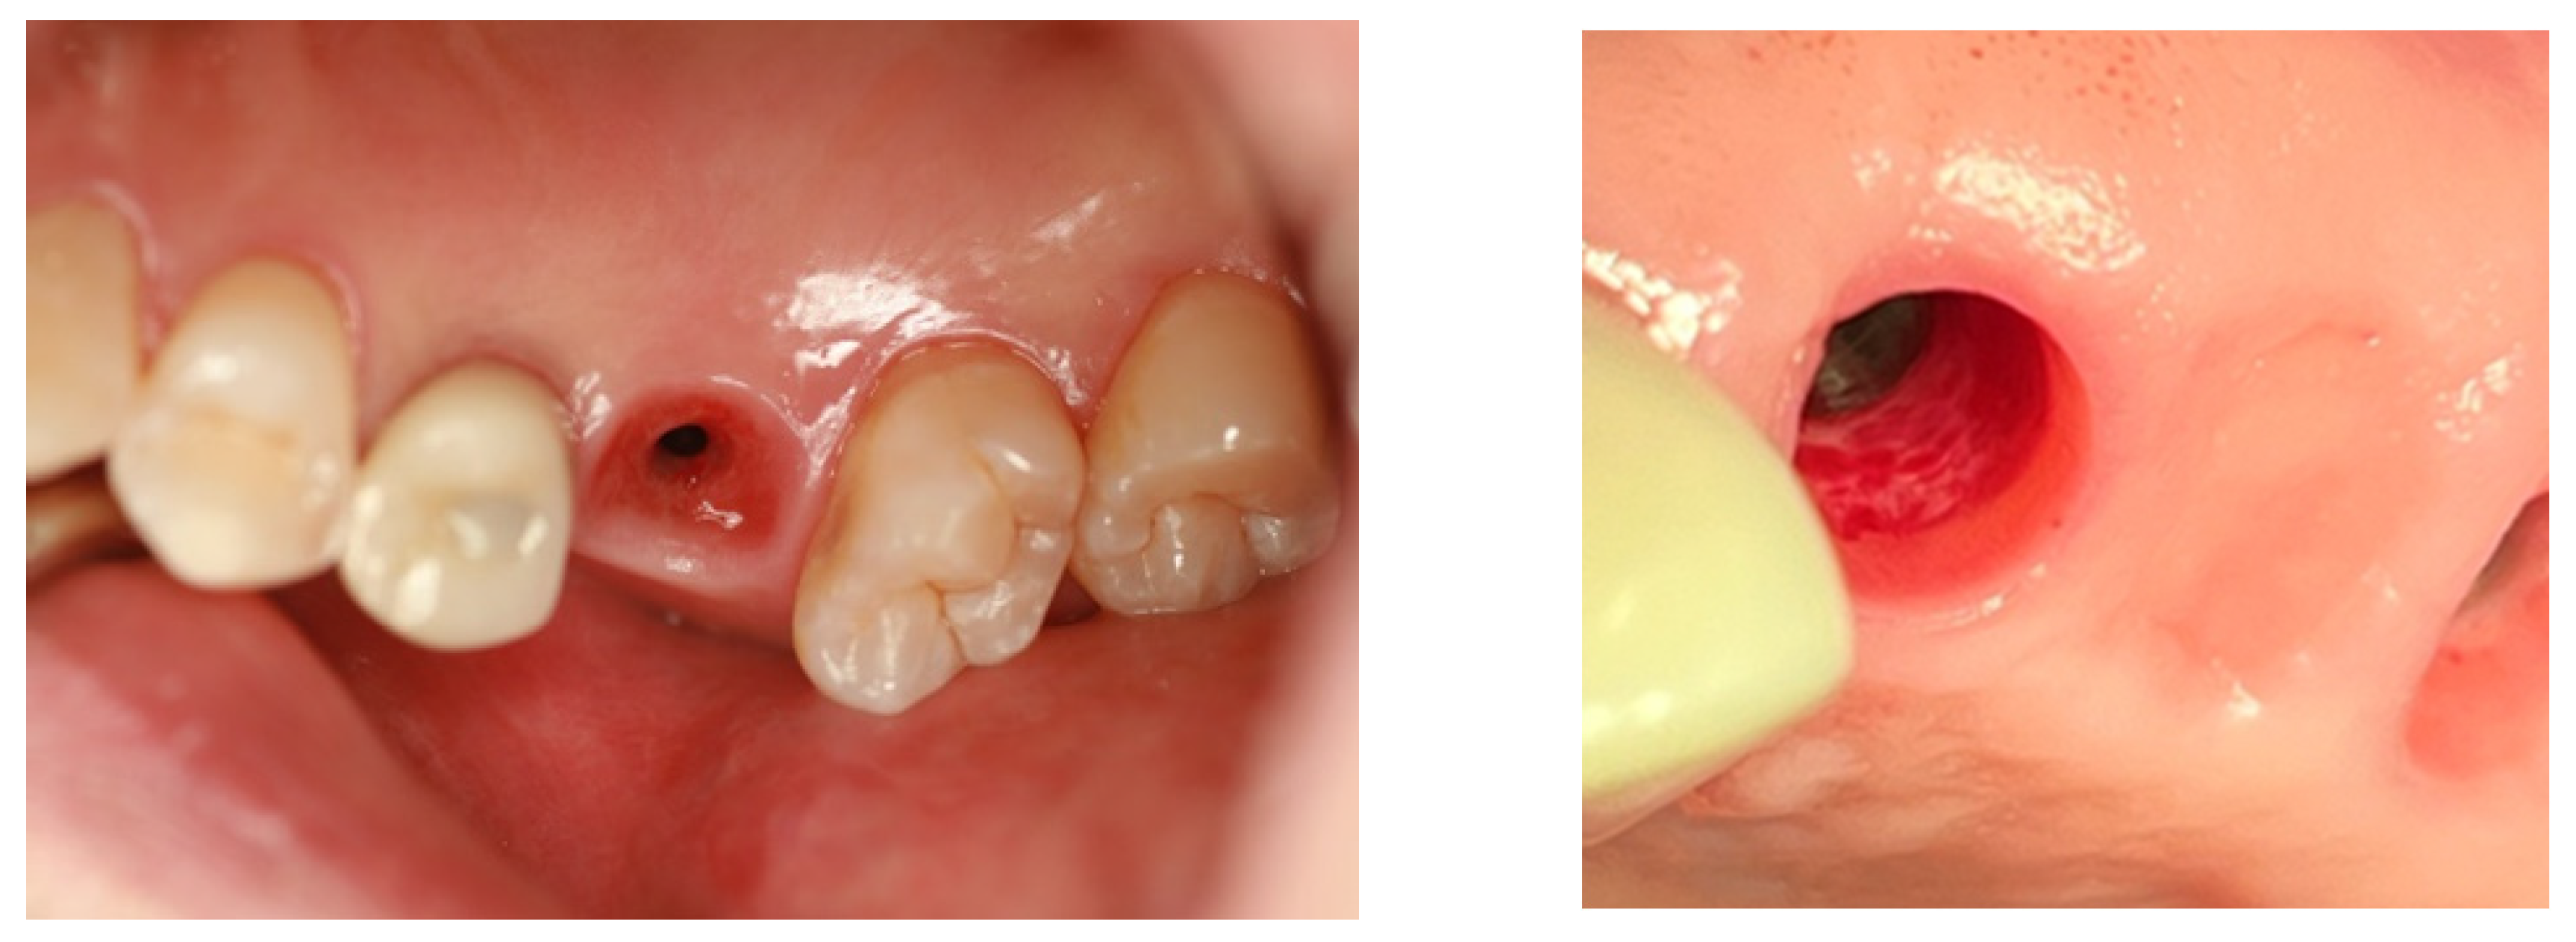

The cases examined in this study demonstrate that the area of transmucosal soft tissue, which corresponds to the junctional epithelium and connective tissue (the biologic width), around dental implants is enlarged due to deep subcrestal placement. This enlargement was quantitatively analyzed using Cone Beam Computed Tomography (CBCT). The results indicated that the average length of the Transitional Zone (TZ) was 3.8 mm, with an average thickness of 0.6 mm. These measurements suggest that the majority of the TZ is composed primarily of connective tissue. As the TZ extends toward the peripheral area and its thickness increases to more than 1.0-1.5 mm, it typically becomes covered with junctional epithelium. The predominant structure of the submucosal area is a connective tissue zone with junctional epithelium primarily present at the entrance, measuring approximately 0.5-1 mm, as detailed by Ikiru Atsuta et al.^[30].

Figure 16. Transmucosal Soft Tissue Structures in Subcrestally Placed Implants. This figure presents clinical images showcasing the transmucosal area related to the junctional epithelium and connective tissue (the biologic width) in subcrestally placed implants (SPIs), captured either after the removal or before the placement of the prosthetic parts. Compared to epi- or equi-crestal implant placements, these SPIs exhibit a larger area of transmucosal soft tissue. The right image distinctly identifies three layers: the subcrestal zone, the Transitional Zone (TZ), and the marginal zone, where the pale pink color closely matches the adjacent oral epithelium.